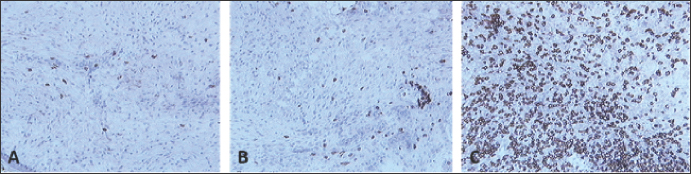

Fig. 2. Skin sections of birds vaccinated with FP9 and stained with monoclonal antibody DF6 against FPV. (A) 2 dpv, (B) 4 dpv, and (C) 6 dpv. Positive stained cells (cells infected with the FPV) appeared brown (100x magnification).

Skin sections from the site of vaccination were stained using a specific monoclonal antibody (DF6) against FPV (Boulanger et al., 2002).

FP9 was detected at two dpv and to a lower degree at 4 dpv. No virus was detected from 6 dpv onwards (Fig. 2).

As there are no lymph nodes in chickens, antigen presentation to lymphocytes may occur within the skin tissue (Lu et al., 2023). From Figures 2 and 3 of the present study, the virus was detected in skin tissue after vaccination at a very high concentration at 2 dpv, to a lower degree at 4 dpv and was almost cleared from 6 dpv. The pattern of macrophage infiltration at the site of inoculation in the skin tissue was similar to that of the virus, in that high numbers were observed at 2 dpv and 4 dpv, and these dropped from 6 dpv onwards (Figs. 4 and 5). The concentration of macrophages in the skin at the site of inoculation was higher than that for the birds which were inoculated with PBSa (negative control) and PHA (inflammatory agent), suggesting that the virus might have been taken up by macrophages. In vitro, PHA stimulates T cell proliferation and differentiation while in vivo, the PHA-skin response is an inflammatory reaction, concerning complex interactions of cells—not only lymphocytes but also macrophages and basophils (Restifo et al., 1994).